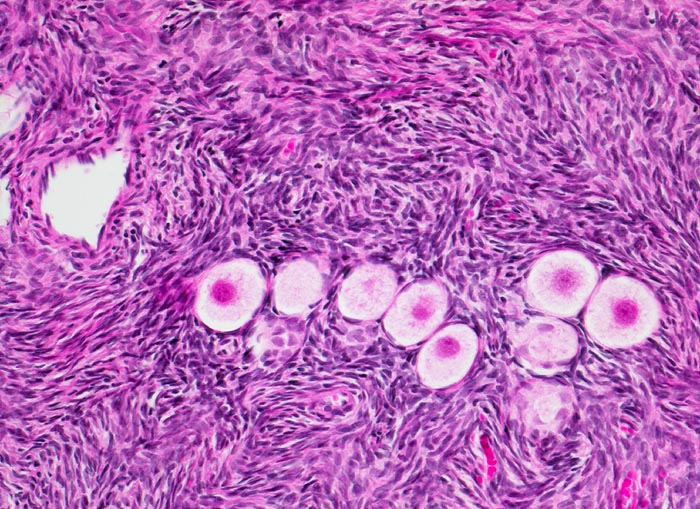

PathoPic – image database / PathoPic ID 4174 - Primordialfollikel in der Ovarrinde

Primordialfollikel in der Ovarrinde

Primordialfollikel umgeben von einer einzelnen Schicht flacher Follikelzellen (spätere Granulosazellen). Die Keimzellen sind eingebettet in ein zellreiches spindelförmiges kortikales Stroma.

Im Verlauf des Lebens geht ein Grossteil der Primordialfollikel zu Grunde ohne eine Narbe zu hinterlassen. Eine Minderheit entwickelt sich weiter und können in jedem Stadium der Entwicklung atresieren.